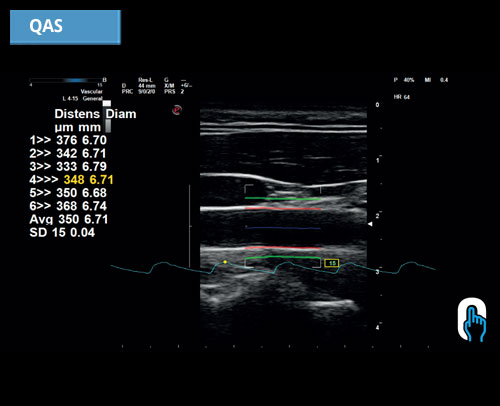

QAS: RF založené automatické měření tuhosti stěny karotidy včetně indexů PWV, CC, AI, , ß.